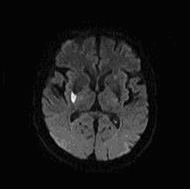

右側大腦阻塞性腦中風(電腦斷層(左)、核磁共振(右))